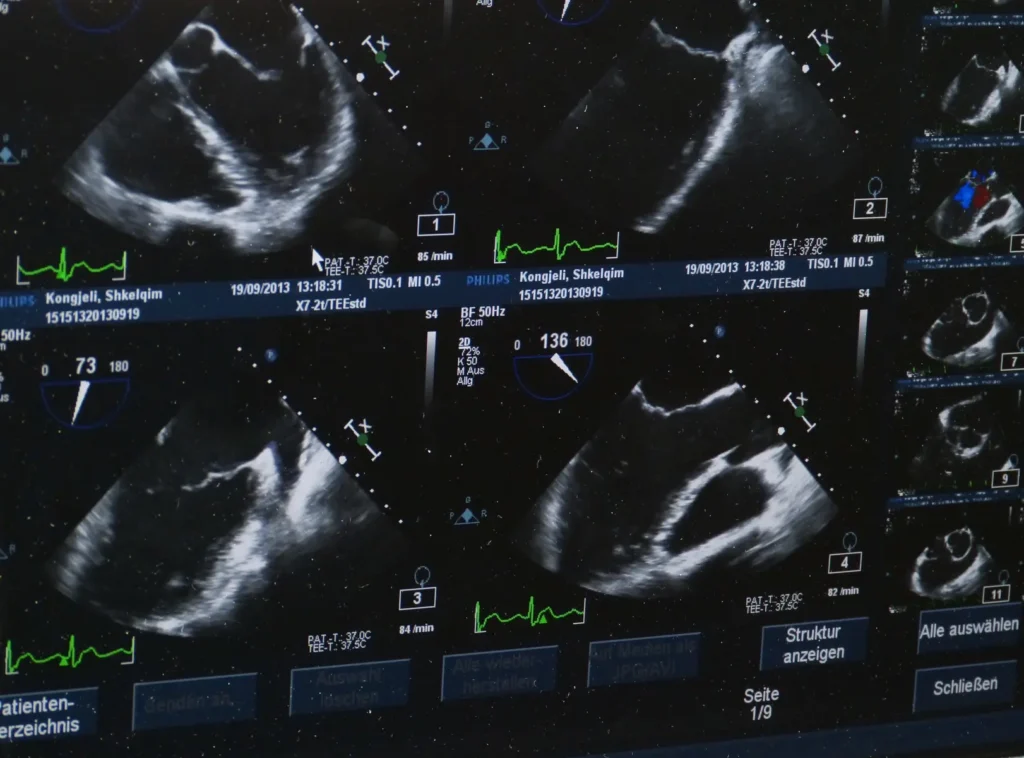

One of the key benefits of USG is its versatility. It is widely used across various medical disciplines, including obstetrics, cardiology, urology, and emergency medicine. In obstetrics, for example, USG plays a critical role in monitoring the development of the fetus, assessing the health of the placenta, and diagnosing potential complications early on. Cardiologists rely on echocardiography, a type of ultrasound, to evaluate heart function, detect abnormalities in heart valves, and diagnose conditions such as heart failure or congenital heart disease.

Moreover, USG’s real-time imaging capability allows for dynamic assessments. For instance, in emergency settings, point-of-care ultrasound (POCUS) can be used to quickly assess trauma patients, guide needle insertions, or evaluate the presence of fluid in the abdomen or lungs. This immediacy is invaluable in critical situations where time is of the essence.